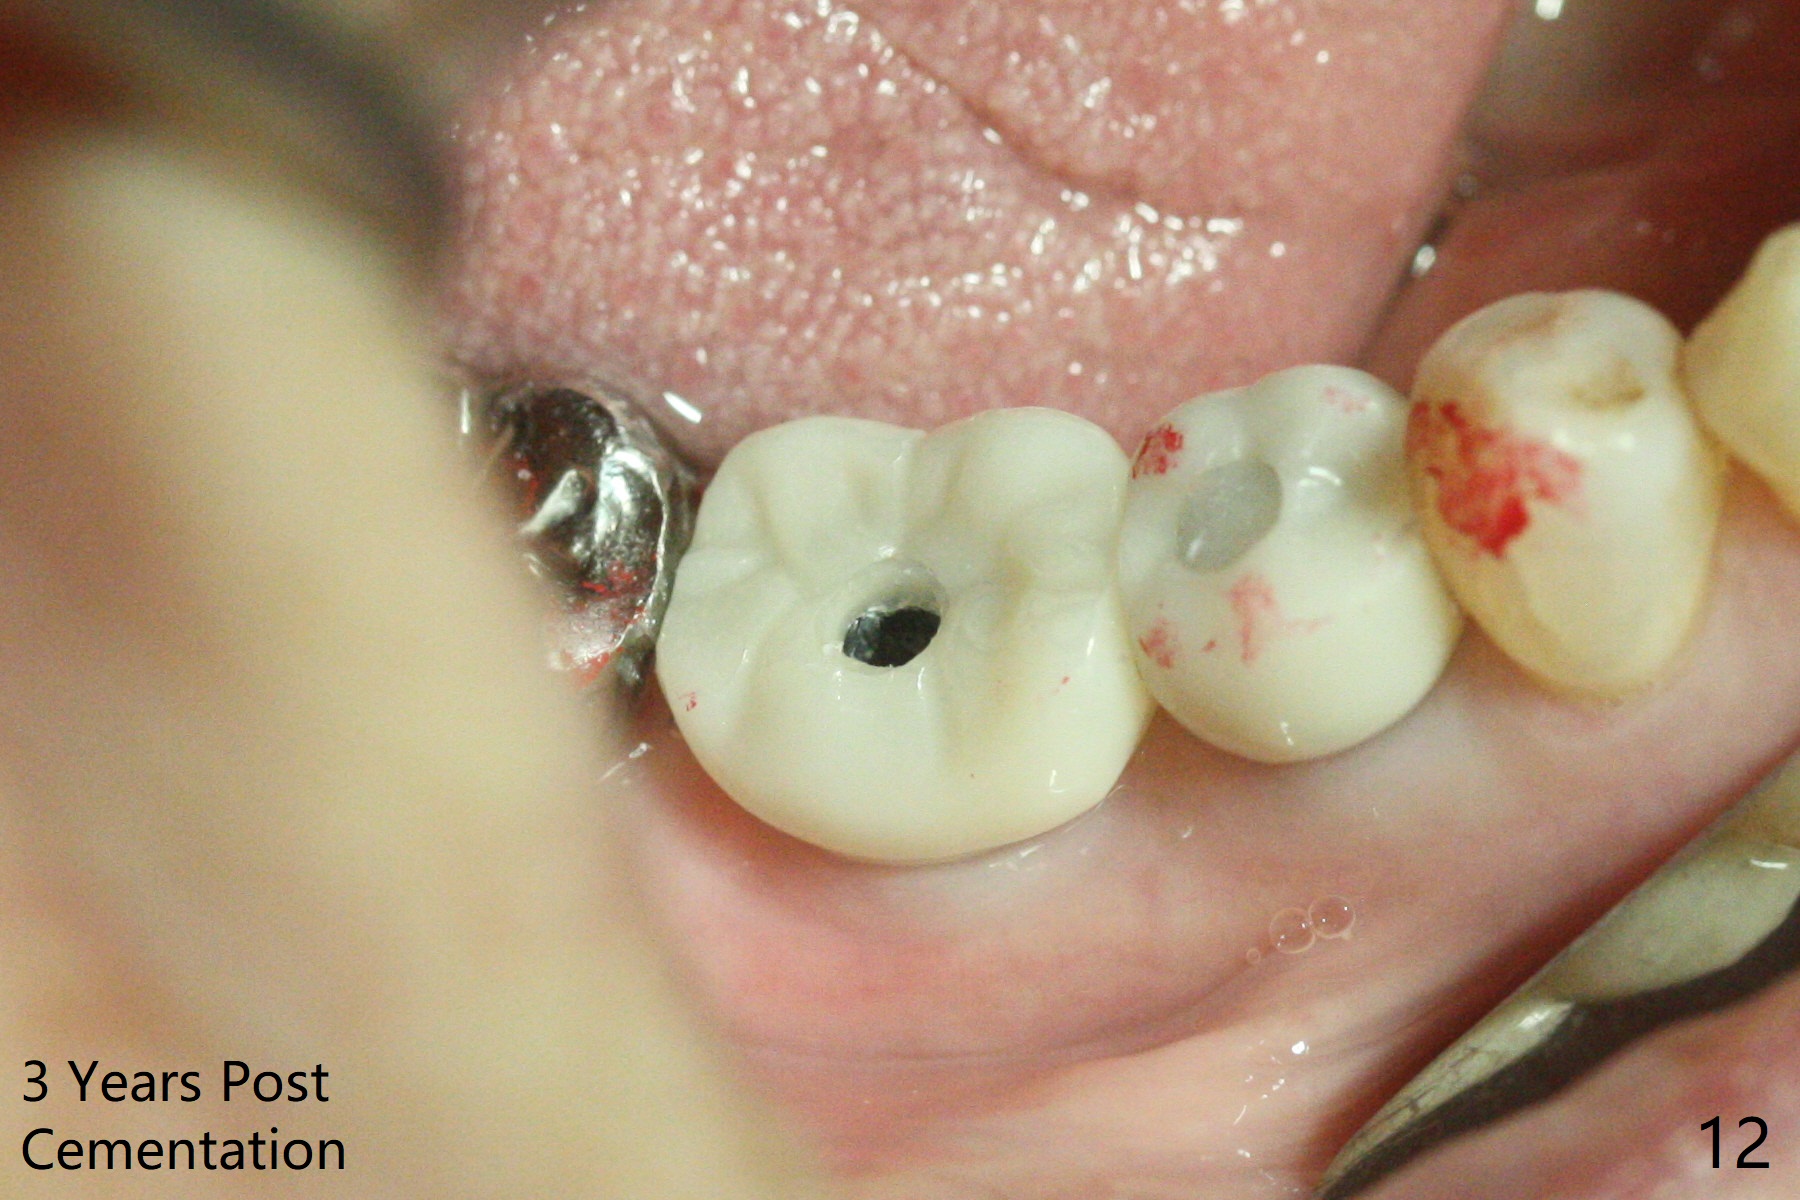

After incision, the ridge at #29 and 30 is found ~ 5 mm wide buccolingually. To place a 4x11 mm IBS implant at #30, the ridge is expanded using BEB technique (bone expansion and bending, Fig.1). It appears that the initial osteotomy at #29 is mesial (Fig.1 yellow dashed line: the distal surface of the root of the tooth #28). After moving the osteotomy distal, the final implant position at #29 (4x11 mm) is within normal limit (Fig.2). The bone at #29 seems to be not so dense that bending (using 1.6 mm drill) is not necessary (using Magic Split and Magic Expanders 3 and 3.8 mm). Later the implant at #30 (4x11 mm) is placed deeper (Fig.3). After placing bone graft around the implants/abutments and suturing, the ridge looks wider with apparent formation of the gingival bands around the abutments (Fig.4 *). Three months and a half postop, bone loss is minimal (Fig.5) and gingival bands forms around the abutments (Fig.6). Fig.7 is taken 1 month post cementation (panoramic X-ray). The patient chews normally 1 year (Fig.8) and nearly 2 years (Fig.9,10) post cementation. The crown at #31 needs recementation 2 years 7 months post #30 cementation; the incomplete seating of the abutment was noted for the first time (Fig.11). Five months later the patient is going to be retired and wants to travel abroad. After approval, the access hole was reopened; articulating paper shows under occlusion of the crown (Fig.12). Since the gap between the abutment and the implant is large, the abutment/crown complex seems to be necessary to be turned (Fig.13 curved arrow). The proximal surfaces of the crown need to be trimmed (straight lines). After turning, the crown sits down with screw tightening; the patient feels pain from the gingival cuff (Fig.14). After turning, the abutment appears to be completely seated (Fig.15). In fact the mesial and distal surfaces of the crown should have clearance from the neighboring teeth (Fig.14) so that pick-up impression is able to hold the crown/abutment complex securely (Fig.16: *). The crown is separated from the abutment after crown repair. They are seated together (loose connection) using the crown as a guide to seat the abutment. BW is taken without the crown. It appears that the abutment remains seated completely (Fig.17). The apical space is equal between #29 and 30 (Fig.17, as compared to Fig.5).